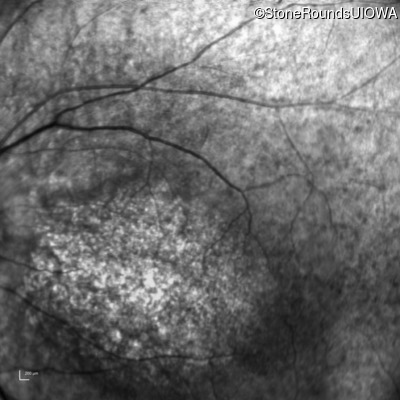

Infrared Fundus Photograph - Left - 10/160 -1

Exemplar